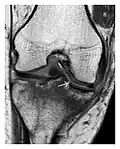

Figure 9: Proximal metaphyseal fatigue fracture of the tibia in a 27-year-old recent male military recruit. (a) Anteroposterior radiograph is within normal limits. (b) Coronal T1-weighted MR image shows a marked linear hypoattenuation along the medial tibial metaphysis (arrow) surrounded by diffuse hypointensity in keeping with posttraumatic edema.[1]